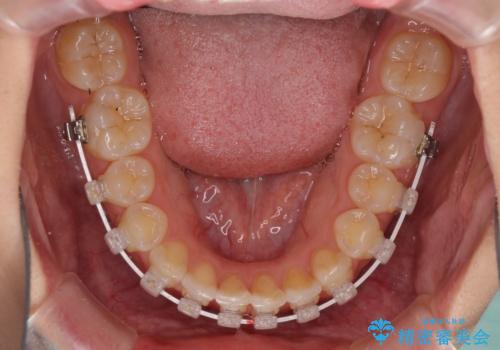

- 審美装置

- 8ヶ月

- 5-10回

下顎は叢生が強かったため、奥歯までワイヤーを装着し、上顎は前歯の一部のみ気になっていたので、その部分にだけワイヤー装置を装着することとしました。